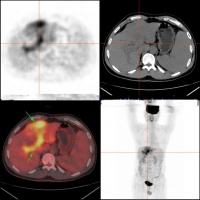

2.B型超生显像可显示直径2cm以上的肿瘤,对早期定位检查有较大的价值;电子计算机X线体层摄影(CT) 可显示直径1.0cm以上的肿瘤;放射性核素扫描 能显示直径3-5cm以上的肿瘤;其它X线肝血管造影、核磁共振像对肝癌诊断有一定价值。

影像学检查